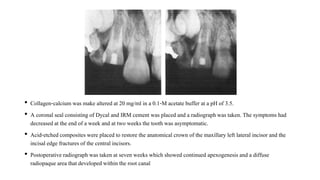

• Collagen-calcium was make altered at 20 mg/ml in a 0.1-M acetatebuffer at a pH of 3.5.

• A coronal seal consistingof Dycal and IRM cement was placed and a radiograph was taken. The symptoms had

decreased at the end of a week and at two weeks the tooth was asymptomatic.

• Acid-etched composites were placed to restore the anatomicalcrown of the maxillary left lateral incisor and the

incisal edge fracturesof the central incisors.

• Postoperative radiograph was taken at seven weeks which showed continued apexogenesisand a diffuse

radiopaque area that developed within the root canal